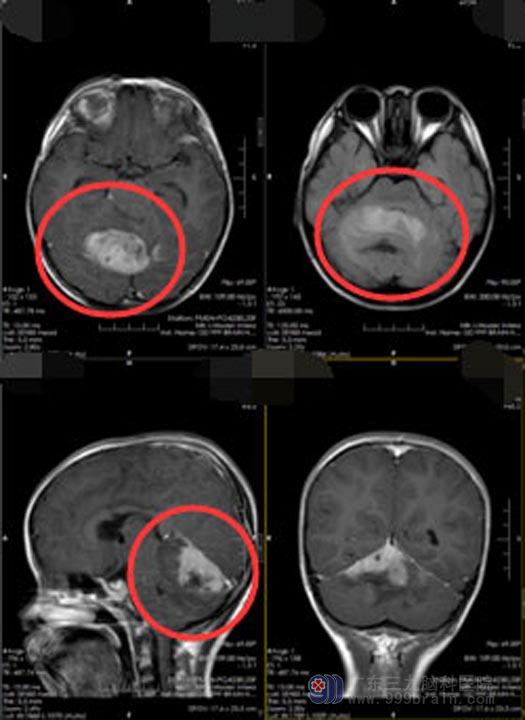

一个月前,妈妈偶然发现杨杨的两侧乳房一大一小,立刻有些紧张了。在当地医院检查,发现杨杨颅内有肿瘤;医生建议去上级医院进一步确诊,在广州市某儿童医院,通过血液内分泌检查及乳房彩超考虑中枢性性早熟,头颅MR示“鞍上-下丘脑病变,考虑错构瘤可能”。

▲手术后